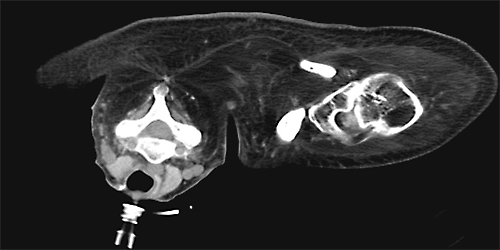

図1.40歳デュシェンヌ型筋ジストロフィー

気管切開にて呼吸管理,ADL全介助,肩関節自動運動不能.

著明な脂肪置換を認めるも一定の筋ボリュームは存在する.